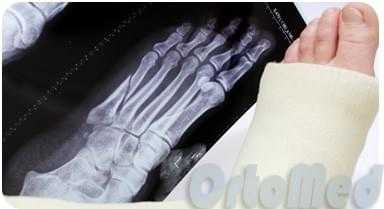

Переломы плюсневых костей - одна из наиболее частых травм стопы. Наиболее часто происходят переломы 5-й плюсневой кости. Переломы плюсневых костей встречаются чаще в социально и экономически активном возрасте, 2-5 декада жизни.

Типичными механизмами травмы являются прямой - падение тяжёлого предмета, раздавливание, или опосредованное воздействие силы - ротация ноги при фиксированном переднем отделе стопы. Другими возможными механизмами становятся избыточное подошвенное сгибание - эквиваленты повреждения Лисфранка, с множественными переломами оснований плюсневых костей, а также стресс-переломы (маршевые переломы), из-за постоянной повторяющейся микротравмы.

Классификация переломов плюсневых костей.

Классификация учитывает локализацию, тип перелома, степень смещения, угол, вовлечение суставных поверхностей, - все стандартные критерии классификации переломов трубчатых костей. Помимо этого можно выделить острые переломы, связанные с однократным воздействием избыточной травмирующей силы, и стрессовые переломы, связанные с функциональной перегрузкой и постоянно повторяющимися микротравмами.